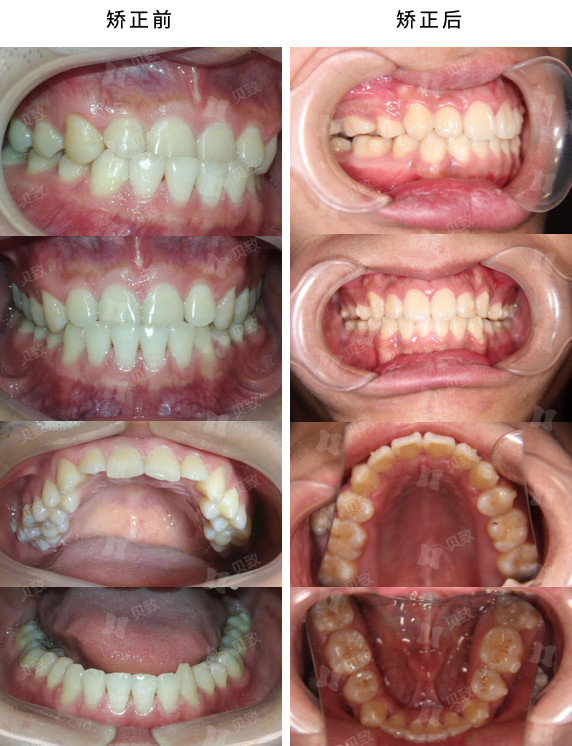

医学类型:反合

矫正方法:隐形矫正

治疗周期:7个月

这个男生正是如此,上唇缩、下巴突、笑起来露不出上牙,只看嘴巴有种“无牙小老头”的感觉。7 个月的矫正后,男生的下巴明显内收,尤其是侧面看,面型改善了很多。

所以通过隐形矫治,内收下前牙,排齐上下前牙,无需拔牙就能解决反颌的问题。

前后对比效果非常明显,前牙反颌问题得到解决,咬合关系恢复正常,不再有“地包天”。男生每次开怀大笑,都会露出一口整齐的牙齿,整个人都变得更加自信了。